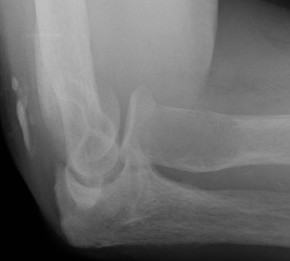

X-ray

Eccentric, sharply demarcated lytic lesion

- no sclerosis around lesion

- narrow zone of transition

- metaphysis, extending into epiphysis

- no mineralization

Differential diagnosis

ABC / UBC

Chondroblastoma - adolescents / areas of calcification

Clear cell chondrosarcoma

Osteosarcoma

Synovial cyst / geode in osteoarthritis